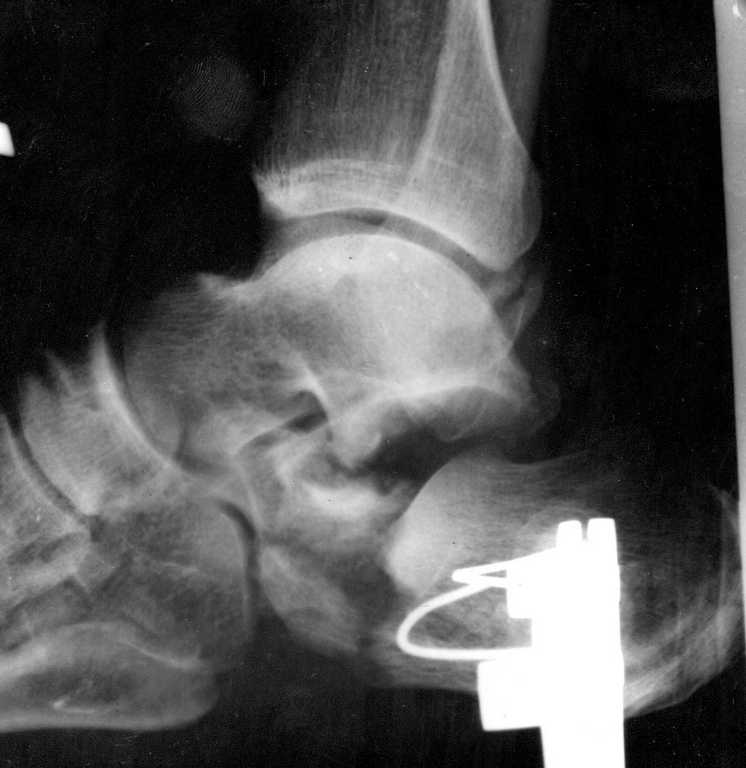

Из личного опыта могу сказать, что всё что в данном случае консервативно или минимизировано, закончится инвалидизацией и негативным отношением пациента к Вам. Можно закрыто выполнить репозицию, но как только, даже в отдалённый период(через 8 месяцев и более)начнётся полноценная нагрузка на конечность кость начнёт проседать со всеми вытекающими.

В качестве примера у себя нашёл снимки больного оперированного около двух лет назад, функция восстановлена полностью, ходит без каких бы то нибыло нарушений, сварщик - работает в полном объёме. Не сохранился первичный снимок, можете поверить на слово перелом примерно аналогичный, как у Вашего пациента.

Другое дело, если действительно не владеете этим способом лечения, у Вас есть время передать больного в другое лечебное учреждение, но это уже решать Вам самому на месте.